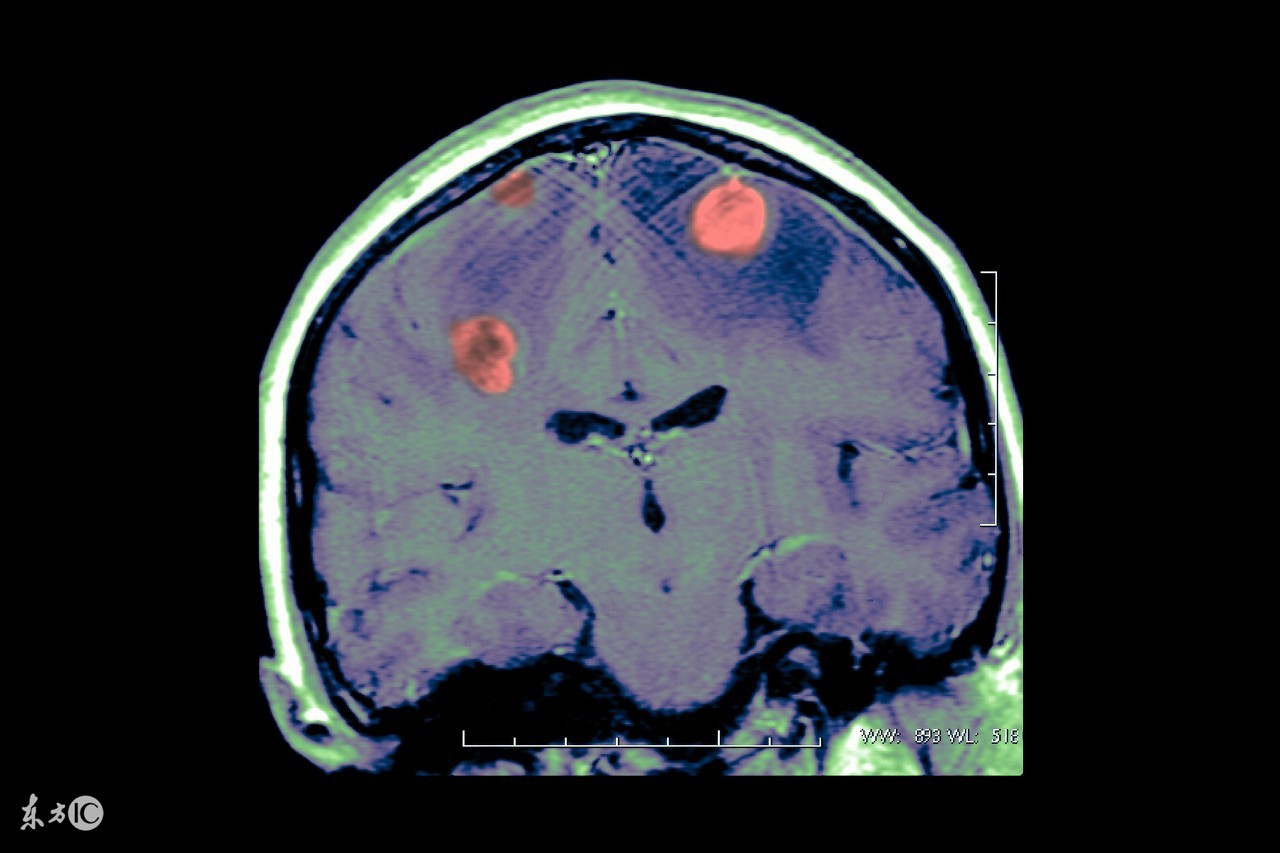

癫痫是慢性反复发作性短暂脑功能失调综合征。以脑神经元异常放电引起反复痫性发作为特征。癫痫是神经系统常见疾病之一,患病率仅次于脑卒中。

儿童癫痫是儿童时间(0-18岁)时期常见的一种病因复杂的、反复发作的、阵发性、暂时性脑功能紊乱所致神经系统综合征。